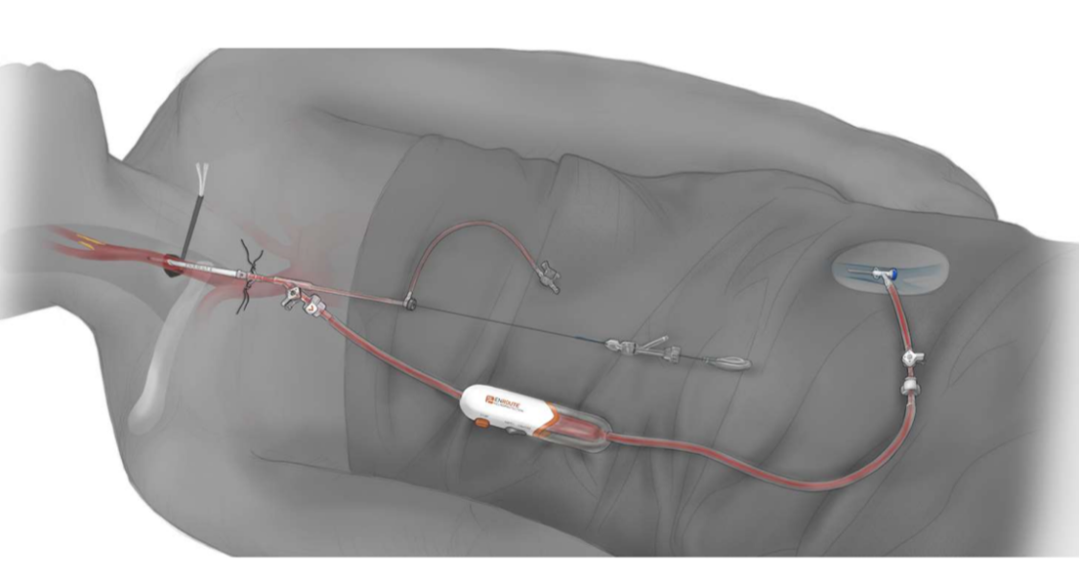

② 脑保护

近端球囊阻断(如TCAR系统)减少栓塞